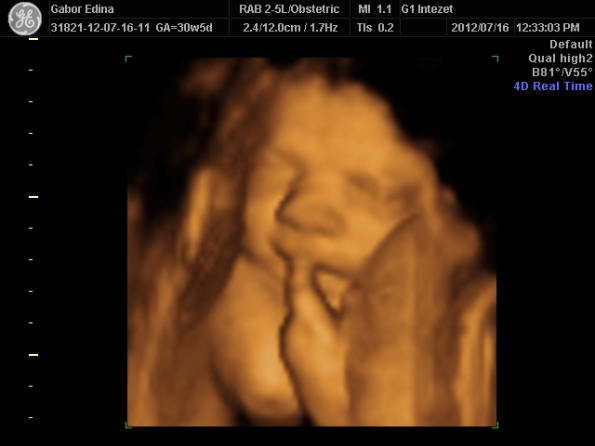

Zso: két baba után most fogalmam sincs Fancsa helyzetéről- most épp bugyi vonalban megy a motoszka, de mind a két oldalon... most nem érzek hüvelybe taposást... talán keresztben van??? vagy terpeszbe

31-én megyek uhu-ra... majd kiderül...